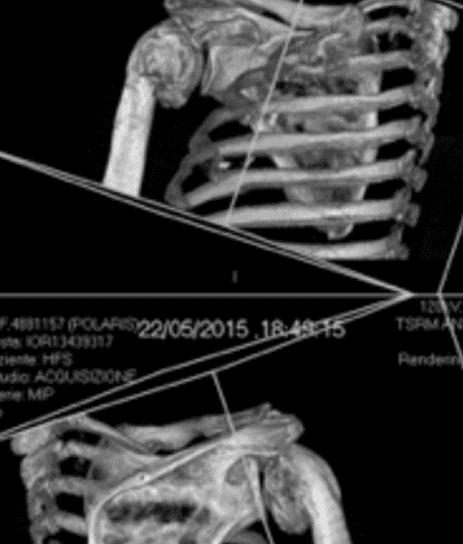

Patient Cases

For fracture and revision treatment

The system offers a set of modular Proximal Bodies in several sizes and heights to be paired with a broad range of Modular Stems, available in different diameters and lengths as well as different surface and coating options for cemented and cementless fixation.

The Proximal Bodies’ spiked surface, together with m-l and a-p holes for suture fixation, allow for stable and physiologic tuberosities reattachment. The modular concept of the fracture components supports the surgeon in achieving adequate joint restoration even in cases with poor anatomical landmarks.1